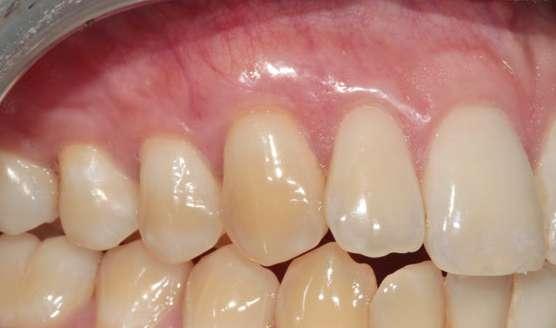

los 6 meses post-operatorio, antes del

10. Seguimiento a 5 años post-operatorio. Obsérvese el buen color, textura y forma gingival, así como la estabilidad de los tejidos blandos aumentados gracias a la excelente higiene oral del paciente y el correcto mantenimiento periodontal.

Figura 8. Seguimiento a

blanqueamiento dental.

Figura

Figura 9. Seguimiento a 12 meses post-operatorio, una vez realizado el blanqueamiento dental domiciliario.

Finalmente, 6 meses después de la cirugía y una vez confirmada la estabilidad de los tejidos blandos, se realizó blanqueamiento domiciliario.

Seguimiento y evolución del caso

Se presentan fotografías clínicas de la evolución y seguimiento a 6 meses, 12 meses y a 5 años (Figs. 8-10). A pesar de una mínima recidiva de menos de 1 mm en la recesión del diente 2.1, es interesante y reconfortante observar la gran estabilidad clínica de los tejidos blandos, así como un color, textura y forma muy armónicos de toda la encía tratada. En gran parte también gracias a un excelente cepillado y mantenimiento periodontal.